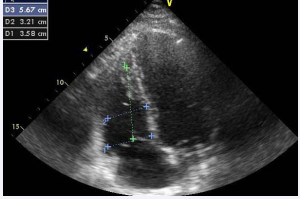

RV dimension is best forecasted at end-diastole from a right ventricle–focused apical 4-chamber view. Care should be taken to get the image demonstrating the maximum diameter of the RV without fore shortening. It can be accomplished by making sure that the crux and apex of the heart are in view (Figure 1).

Figure 1: Measure of RV Dimension (Basal-D1, mid-D2 and longitudinal-D3 diameters).

RV diameter > 35 mm at themid-level and > 42 mm at the base and states RV dilatation. Like wise, longitudinal dimension > 86 mm indicates RV enlargement [1].